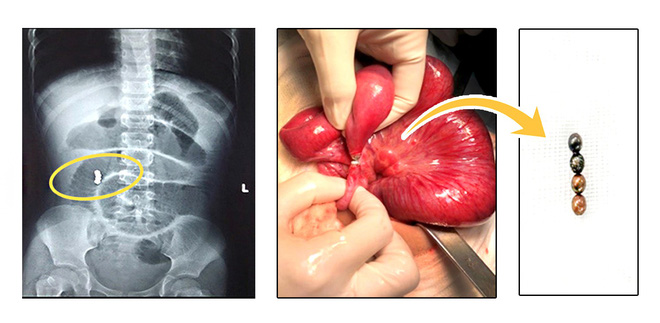

Trên phim X-Quang bụng phát hiện thấy 4 dị vật cản quang hình tròn. Bệnh nhi đã được các bác sĩ tiến hành phẫu thuật khẩn cấp và lấy ra 4 viên bi nam châm nằm ở ruột non và manh tràng. Các viên bi dính chặt nhau làm thủng ruột 4 nơi nên phải cắt lọc và khâu lại.

Trên phim X-Quang bụng phát hiện thấy 4 dị vật cản quang hình tròn.